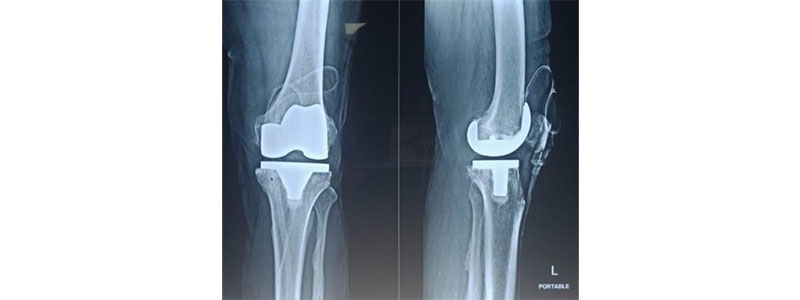

Knee replacement surgery is a procedure that involves replacing a damaged knee joint with an artificial implant.

Knee replacement surgery takes around one hour and involves removing the damaged cartilage and bone from the joint and replacing them with artificial metallic implants. These implants can be placed in different parts of the knee: the lower end of the femur (metal cobalt-chronium or Titanium piece), the upper end of the tibia ( metal cobalt-chronium / titanium piece), or at the back of the kneecap (made of strong plastic).